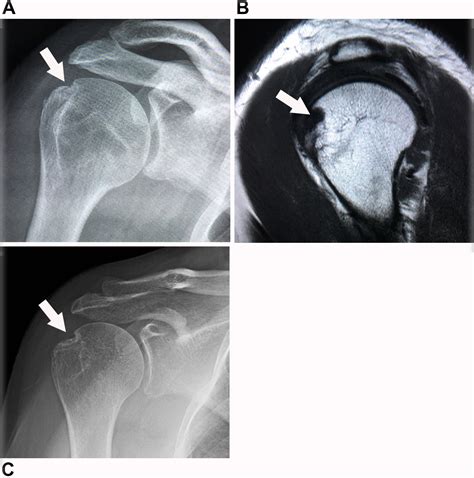

• Imaging studies: X-rays, MRI, or CT scans may be used to visualize the shoulder joint and confirm the presence of a Hill Sachs Lesion. These imaging studies can also help determine the size and location of the lesion, which is important for treatment planning.

In some cases, additional tests, such as arthroscopy, may be necessary to fully evaluate the extent of the injury and plan appropriate treatment.